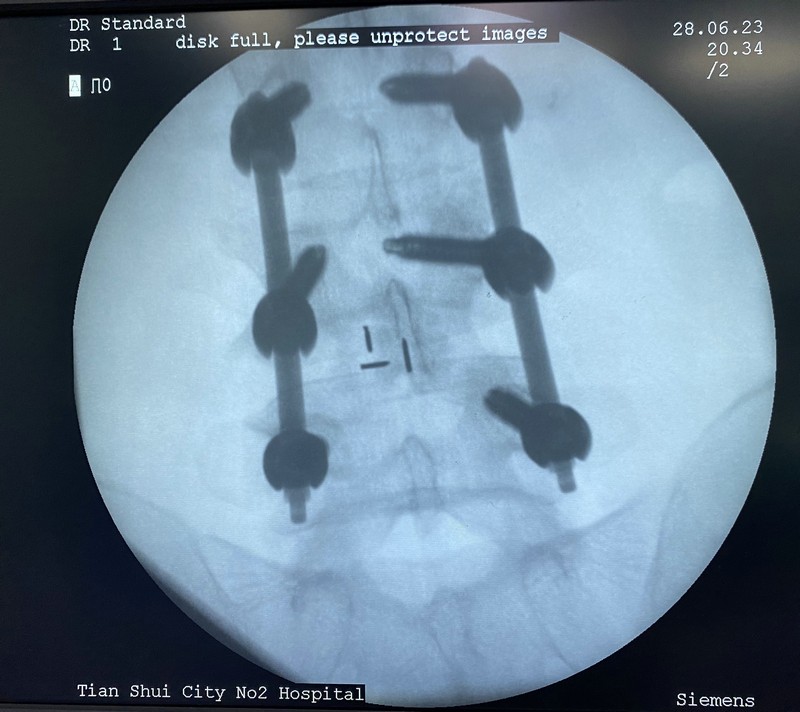

患者王某某,女,49歲,該患者5年無明顯誘因出現(xiàn)腰部疼痛伴左下肢放射痛、麻木不適,予以針灸、理療等對癥治療,病情時(shí)輕時(shí)重。3月前勞累后再次出現(xiàn)上述癥狀,且癥狀進(jìn)行性加重,嚴(yán)重影響生活,聽村民介紹后到市二院骨傷科三病區(qū)就診。經(jīng)檢查后,腰椎動(dòng)力位片提示腰椎不穩(wěn);腰椎核磁提示腰4/5椎間盤巨大突出,腰4/5椎管狹窄。副院長姚雄兵帶領(lǐng)骨三科團(tuán)隊(duì)立即組織病例討論,仔細(xì)詢問病史及體格檢查,結(jié)合影像學(xué)檢查,全面評估后與患者及家屬溝通,確定行“經(jīng)皮脊柱內(nèi)鏡輔助下腰椎椎體間植骨融合內(nèi)固定(ENDO-PLIF)術(shù)”。手術(shù)邀請甘肅中醫(yī)藥大學(xué)附屬醫(yī)院椎間盤中心主任李元貞指導(dǎo),在手術(shù)麻醉科的配合下術(shù)程順利,術(shù)后患者左下肢放射痛、麻木癥狀完全緩解,手術(shù)效果良好。

與傳統(tǒng)的腰椎后路開放減壓手術(shù)及通道下的MIS-TLIF手術(shù)相比,經(jīng)皮脊柱內(nèi)鏡后路腰椎ENDO-PLIF手術(shù),創(chuàng)傷更小,神經(jīng)根及硬膜囊顯露清晰,且最大限度的保護(hù)了脊柱骨骼、韌帶及肌肉的完整性,對脊柱穩(wěn)定性影響較小,術(shù)后患者感受更佳,康復(fù)更快,脊柱的ENDO-PLIF微創(chuàng)手術(shù)必將成為未來的發(fā)展趨勢。